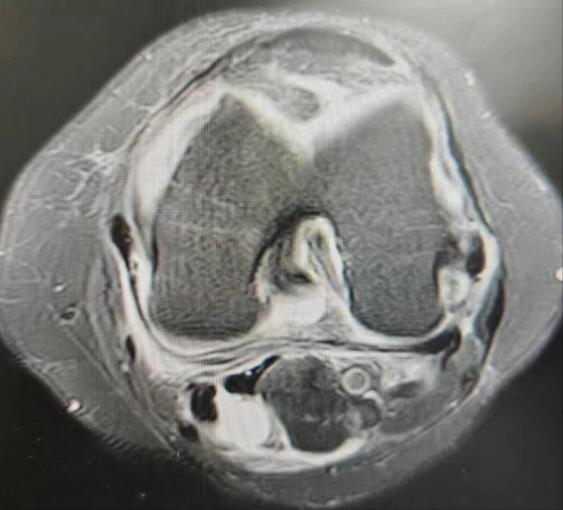

病例1,患者左膝关节疼痛不适半年,行经查体及MRI检查诊断为:左膝内侧半月板损伤、腘窝囊肿、骨性关节炎,给予行“左膝关节镜下内侧半月板、软骨修整成形及腘窝囊肿切除术”。

病例2,患者左膝关节疼痛不适2月,经查体及MRI检查诊断为:左膝内外侧半月板损伤、腘窝囊肿、骨性关节炎,考虑囊肿较小,且为单房囊肿,行“膝关节镜下半月板、软骨修整成形术”的同时,给予切除“活瓣”,行“腘窝囊肿减压术”。

腘窝囊肿又叫“Baker囊肿”,分为原发性和继发性两种,前者儿童多见,后者中老年多见,绝大多数的腘窝囊肿继发于膝关节内病损,包括半月板损伤、骨关节炎、类风湿关节炎、色素沉着绒毛结节性滑膜炎等。发病原理是单向流通的“活瓣”(只进不出),即腘窝囊肿通道口存在的皱襞、束带或关节内疾患堵塞通道口,增多的关节积液可通过通道进入滑囊,但不能从滑囊回到关节腔,导致囊肿的形成和持续存在。目前膝关节镜下腘窝囊肿切除术已成为主流手术方式,关节镜下不仅能切除囊肿,还能处理半月板损伤、骨关节炎等关节内疾病,大大降低了复发的几率。